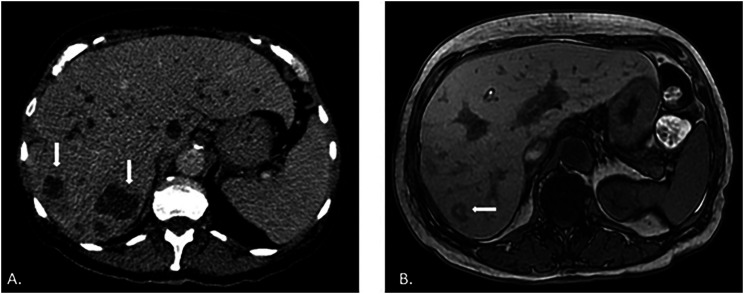

副球孢子菌病是拉丁美洲最重要的全身性真菌病,与农村活动密切相关。在巴西,它是一种地方病,估计每年有 4000 到 6000 个病例,占全球诊断病例的 80% 以上。我们介绍了一例罕见的病例,患者是一名 71 岁的妇女,以肠道表现为主。盲肠阑尾受累导致了胆管炎并发症,其症状与胆管癌相似。

Paracoccidioidomycosis, the most important systemic mycosis in Latin America, is closely linked to rural activities. In Brazil, it is an endemic disease, with an estimated 4,000 to 6,000 annual cases, accounting for over 80% of the global diagnoses. We present an intriguing case of this disease with an intestinal manifestation in a 71-year-old woman. The involvement of the cecal appendix led to a complication of cholangitis that mimicked cholangiocarcinoma.